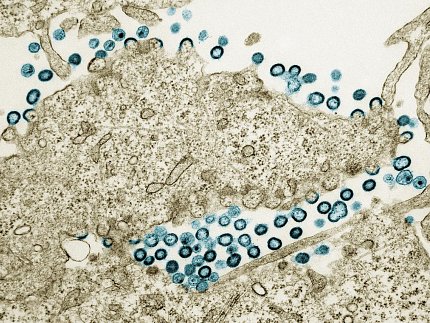

Transmission electron micrograph of HIV-1 virus particles (teal) budding and replicating from a segment of a chronically infected H9 cell (tan).

Photo:  NIAID